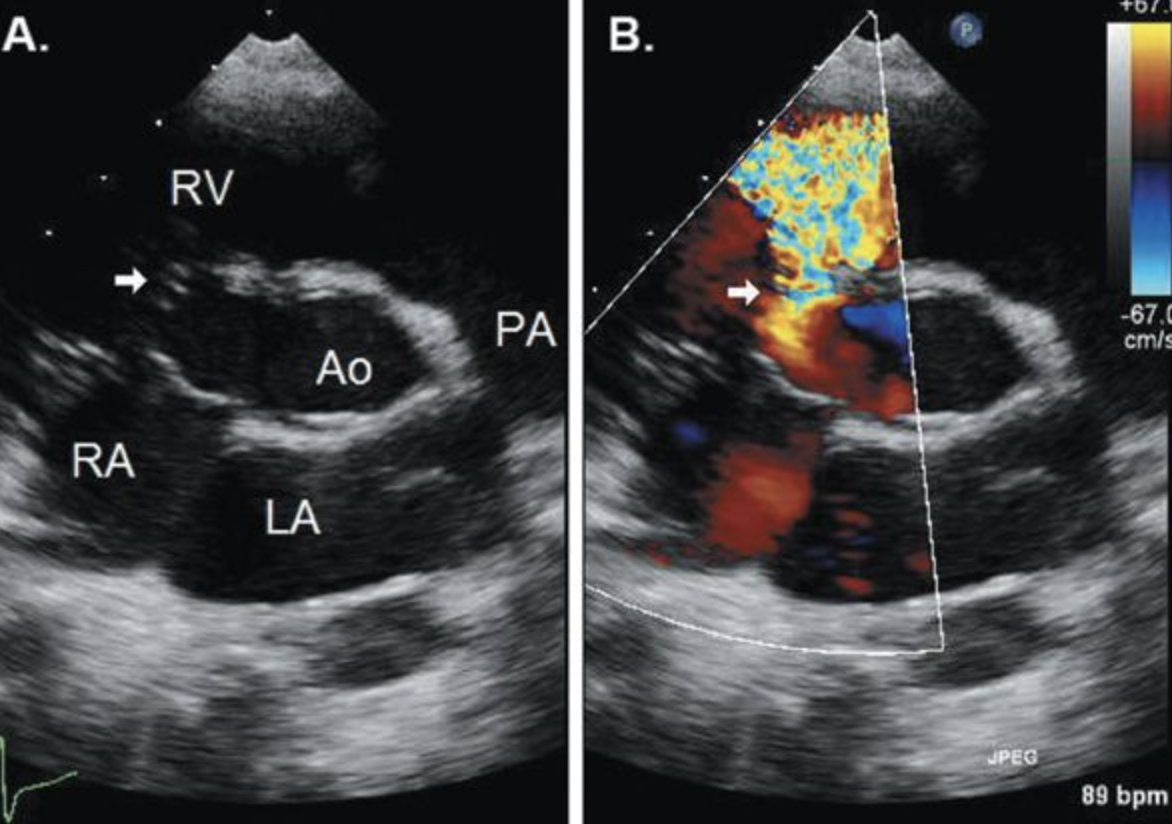

22

Q

What specific kind of VSD is this?

A

Gerbode Defect